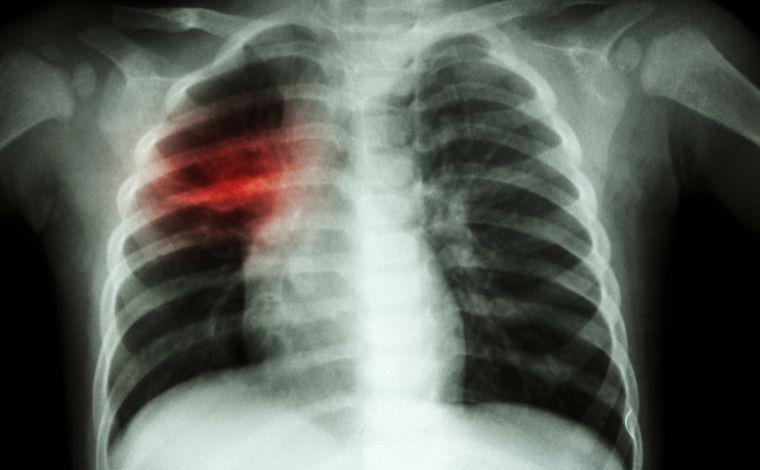

"O outro estigma, já histórico, é a tosse. Uma tosse crônica, por mais de três semanas, que faz às vezes o paciente expectorar sangue por comprometimento pulmonar. É a chamada de 'tosse de tuberculoso'."